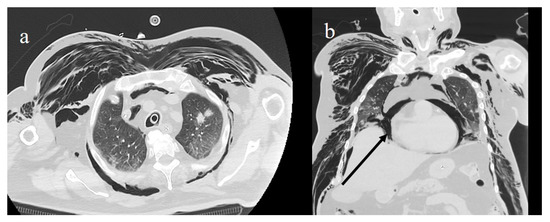

4.3. COVID-19 CT Features and Reporting System

- Li, K.; Fang, Y.; Li, W.; Pan, C.; Qin, P.; Zhong, Y.; Liu, X.; Huang, M.; Liao, Y.; Li, S. CT image visual quantitative evaluation and clinical classification of coronavirus disease (COVID-19). Eur. Radiol. 2020, 30, 4407–4416. [Google Scholar] [CrossRef] [PubMed] [Green Version]

- Fu, F.; Lou, J.; Xi, D.; Bai, Y.; Ma, G.; Zhao, B.; Liu, D.; Bao, G.; Lei, Z.; Wang, M. Chest computed tomography findings of coronavirus disease 2019 (COVID-19) pneumonia. Eur. Radiol. 2020, 30, 5489–5498. [Google Scholar] [CrossRef]

- Ojha, V.; Mani, A.; Pandey, N.N.; Sharma, S.; Kumar, S. CT in coronavirus disease 2019 (COVID-19): A systematic review of chest CT findings in 4410 adult patients. Eur. Radiol. 2020, 30, 6129–6138. [Google Scholar] [CrossRef]

- Zhou, S.; Zhu, T.; Wang, Y.; Xia, L. Imaging features and evolution on CT in 100 COVID-19 pneumonia patients in Wuhan, China. Eur. Radiol. 2020, 30, 1–9. [Google Scholar] [CrossRef] [PubMed]